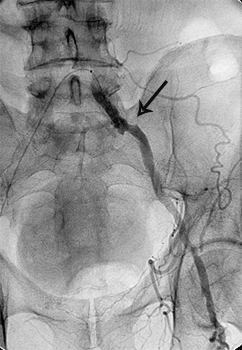

Приклади ангіограм до та після дилятації:

стеноз лівої клубової артерії    балон, роздутий в зоні стенозу    відновлення отвору клубової артерії

Значний стеноз лівої

наружної клубової артерії